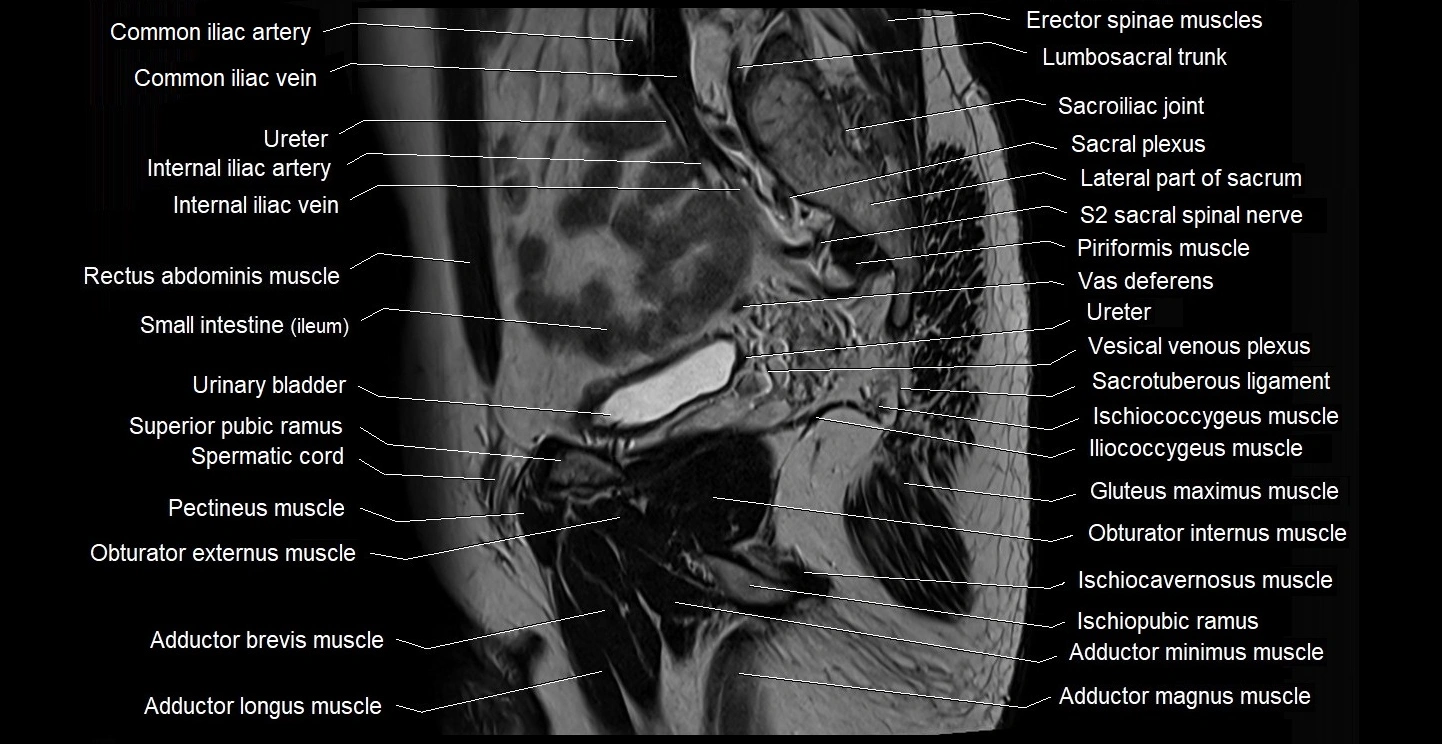

- Adductor brevis muscle

- Adductor longus muscle

- Adductor magnus muscle

- Adductor minimus muscle

- Internal iliac artery

- Internal iliac vein

- Lumbosacral trunk

- Obturator externus muscle

- Pectineus muscle

- Piriformis muscle

- Psoas major muscle

- Sacral plexus

- Sacroiliac joint

- Sacrotuberous ligament

- Sartorius muscle

- Spermatic cord

- Superior pubic ramus

- Vas deferens